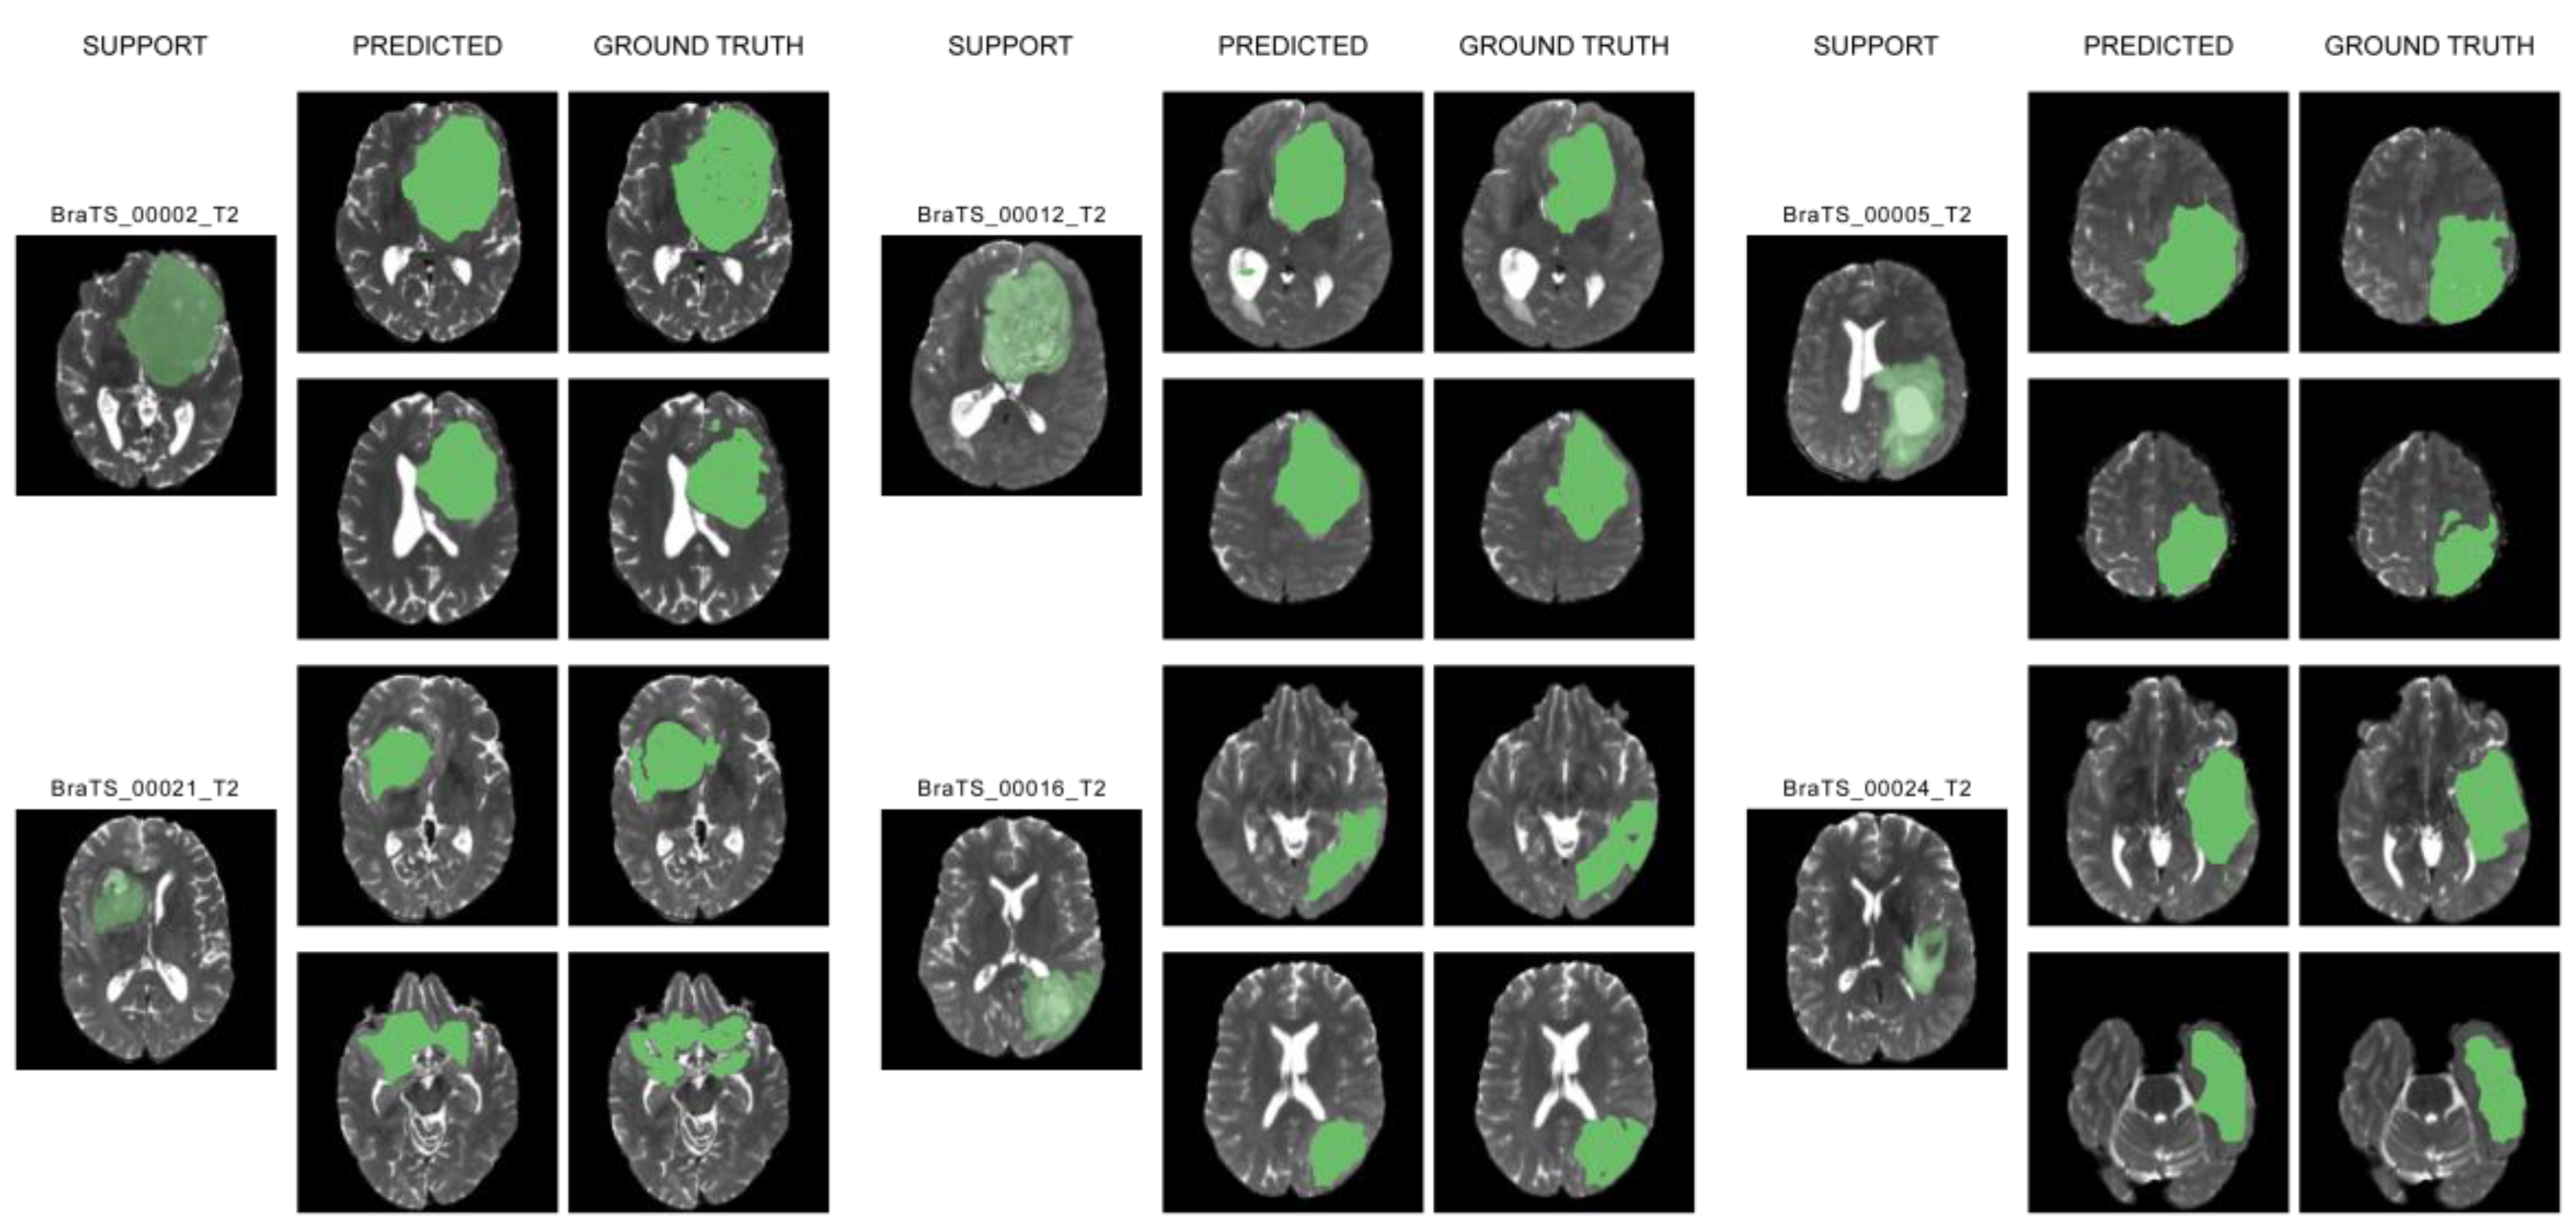

4.1. Dataset